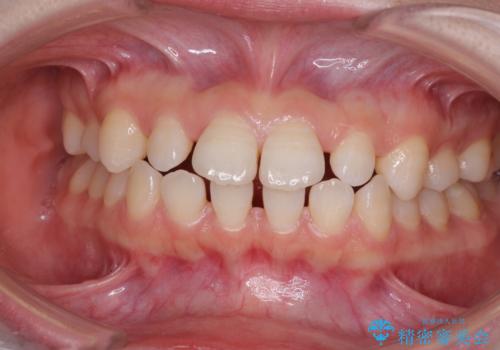

欠損と残存乳歯 矯正治療とインプラント治療